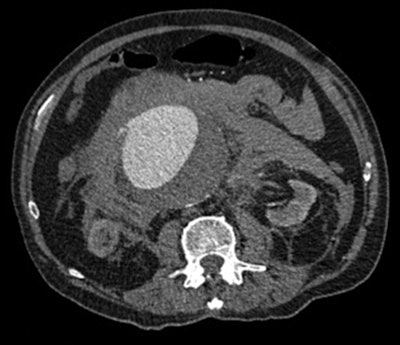

Acute abdominal pain outside of the trauma setting is common in the emergency department, with a wide spectrum of underlying causes for which CT is used as an integral part of surgical triage, the authors noted.

"Emergency abdominal or abdominopelvic CT performed out of hours in acutely ill patients is a complex investigation with the potential to impact positively or negatively on patient outcomes depending on the accuracy and timeliness of the report," they wrote.